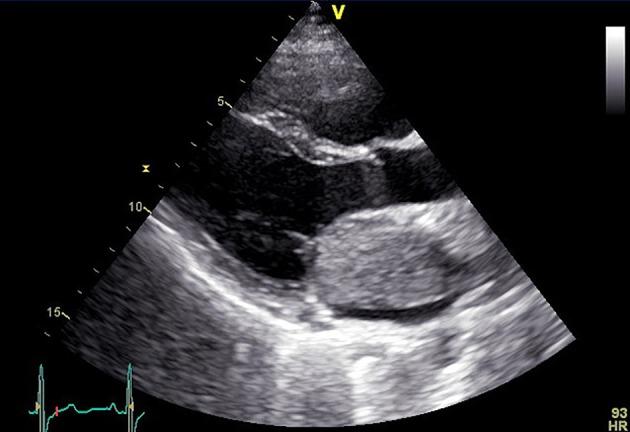

Myxoma is the most common primary cardiac tumor and is usually located in the left atrium. Clinical manifestation relies in large part on the size, location, and architecture of the tumor. There are many reports in the literature of cardiac myxomas causing syncope, embolism, even myocardial infarction. We present a rare case of a patient who underwent urgent surgical resection of a large left atrial myxoma mimicking mitral stenosis. The postoperative course of the patient was uncomplicated. One year after surgery, the patient is asymptomatic and disease-free.

黏液瘤是最常见的原发性心脏肿瘤,通常位于左心房。临床表现很大程度上取决于肿瘤的大小、位置和结构。文献中有许多关于心脏黏液瘤导致晕厥、栓塞甚至心肌梗死的报道。我们报告一例罕见病例,患者因酷似二尖瓣狭窄的巨大左心房黏液瘤接受了紧急手术切除。患者术后过程顺利。术后一年,患者无症状且无疾病复发。